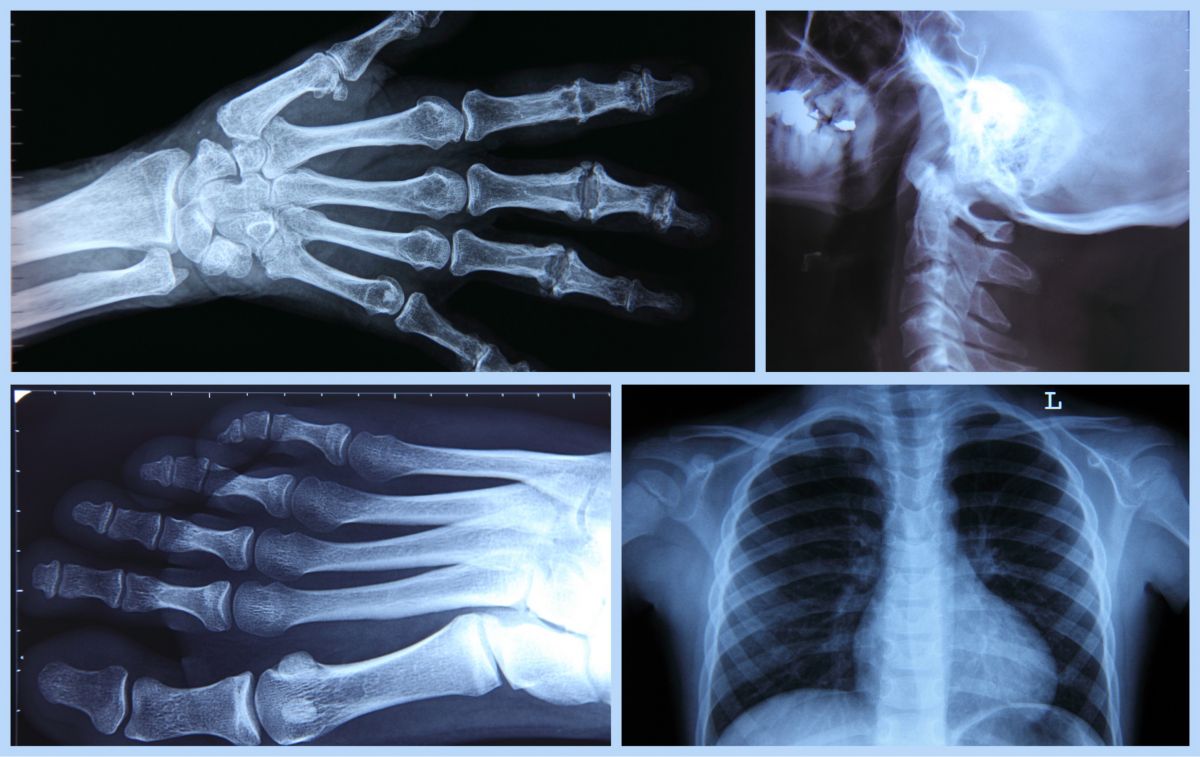

radiologie-imagerie-medicaleL’établissement dispose d’un plateau technique permettant l’accès à des actes d’imagerie médicale conventionnelle. Ce service de téléradiologie est accessible aux patients hospitalisés et à l’ensemble de la population du territoire sur rendez-vous.

Ils réaliseront les clichés conformément à la prescription d’examens de radiologie qui vous aura été établie. Ils les transmettront via un service de téléradiologie au Centre Hospitalier Comminges Pyrénées pour interprétation ensuite par un médecin radiologue. Un compte-rendu sera transmis à l’équipe médicale du service où vous êtes hospitalisé ou à votre médecin traitant pour les externes.